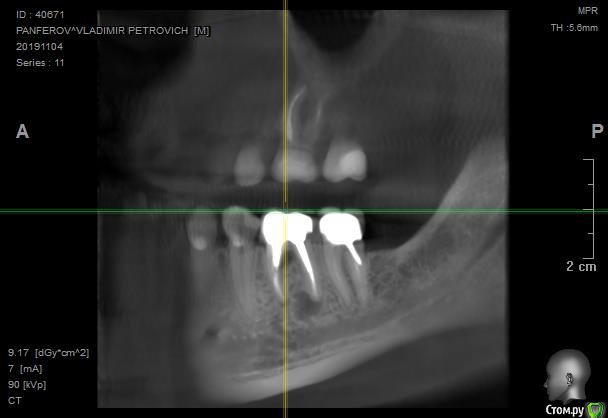

в 2011-м году 6-й снизу справа зуб был депульпирован, спустя несколько лет установлена коронка с ВКВ

Перед заменой коронки на соседнем зубе сделали контрольный снимок, обнаружили кисту.

Лечащий врач считает невозможным извлечь ВКВ. С учетом того, что зуб не беспокоит предложила сделать контрольный снимок через год и там принимать решение об удалении в зависимости от роста кисты.

Если мы рассуждаем о жизнеспособности данного (6-го) зуба, то его прогноз ухудшается наличием процесса между корнями в первую очередь, а кистой во вторую.

Уверен на 90%, что извлекая вкладку из данного зуба, ему можно подписать приговор на удаление.